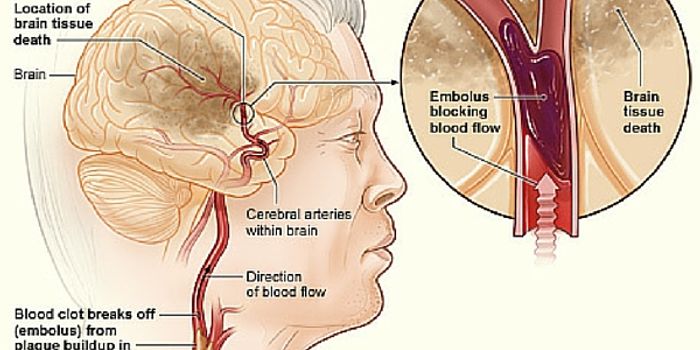

MAR 21, 2016NeuroscienceThe most common kind of stroke, an ischemic stroke, is caused by a blood clot which blocks the flow of oxygenated blood ...

APR 27, 2016NeuroscienceStroke is the fifth leading cause of death in the US and the leading cause of both short and long-term disability. ...